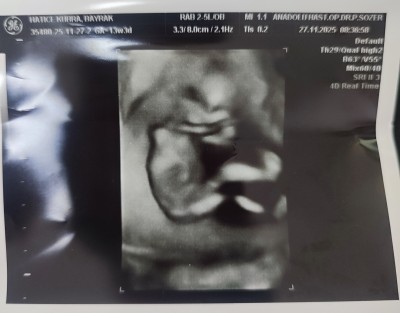

11 haftalık ve 13+5 haftalık ultrason görüntülerimiz doktor cinsiyette emin olamadi önce erkek sonra kız dedi ama sizin tahminleriniz neler?

Gebelik haftası 13+5

Bacak arasında uç cızgı var gıbı canm kıza benzettim bende

Kız hissettim

Kız sanki☺️